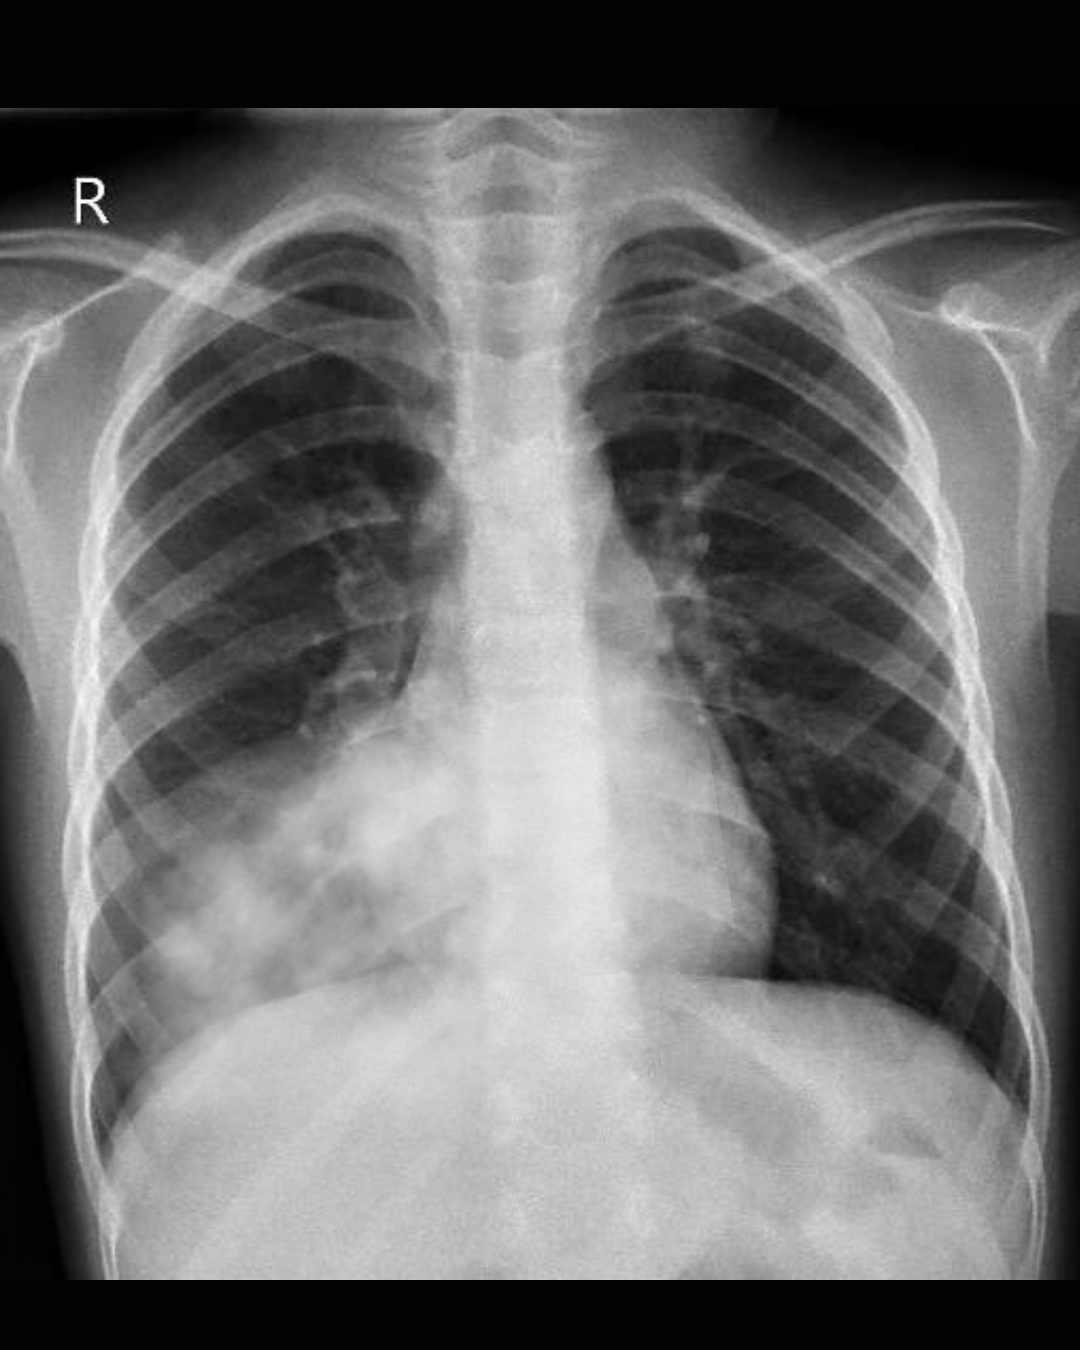

Consolidación pulmonar: Área del pulmón donde los alvéolos están llenos de material inflamatorio en lugar de aire, visible en radiografías.

Bronconeumonía: Tipo de neumonía que afecta principalmente los bronquiolos y alvéolos adyacentes, con distribución parcheada.